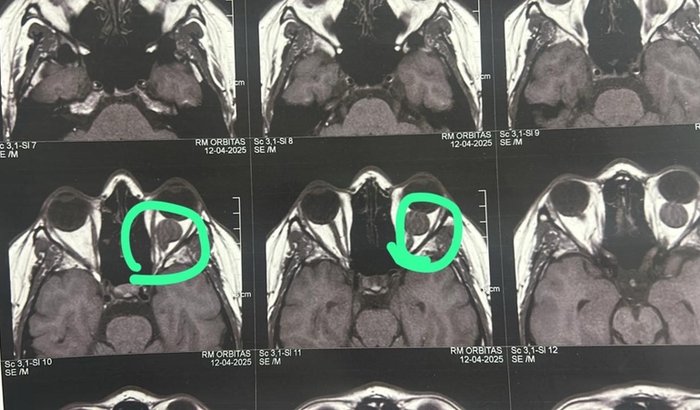

Olá amigos!Me chamo Jaqueline tenho 31 anos e moro em Itu/SP. Em 2014 fui diagnosticada com um miningioma de nervo óptico no meu olho esquerdo, o qual me fez perder toda visão desse olho.Na ocasião foi sugerido o acompanhamento.Ele se manteve estável por 10 anos, porém em abril deste ano, na ressonância manifestou um aumento, provavelmente por conta de um tratamento que realizei para engravidar, a carga de hormônios fez com que ele tomasse impulso e crescesse.No retorno ao médico foi sugerido a remoção através de uma craniotomia.Tentamos pelo convênio, porém sem sucesso e uma briga judicial não é uma alternativa.Hoje uma cirurgia desse porte fica em média 230 a 240 mil reais, e nós não temos condições de arcar com esse valor!O médico me deu 6 meses para conseguir ajustar as condições para me operar, e já se passaram 4 meses, colocamos nossa casa a venda, mas não obtivemos sucesso, ela também é financiada, e o valor de “sobra” seria insuficiente, hoje o que tenho é a fé em Deus que vamos conseguir!Alguns amigos sugeriram a vaquinha online, e estou aqui para pedir sua ajuda!Desde já, quero agradecer, a todos que de alguma forma puderem me ajudar, seja compartilhando esse vídeo, com algum valor, e o principal, me ajudando em oração! 🙏 Não está sendo nada fácil, ainda algumas situações são incertas, mas eu creio que Deus, está cuidando de mim, em detalhes!Que o Senhor retribua na vida de cada um de vocês! Obrigada!Com amor e gratidão, Jaque! ♥️